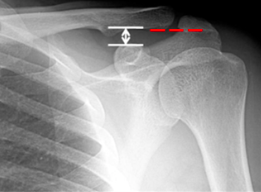

In normal configuration, the inferior cortices of the clavicle and acromion are in alignment (Figure 3). Additionally, the coracoclavicular distance is normally less than 13 mm or there is a less than 5 mm difference between the left and right coracoclavicular distances. (1; 3) Figure 4 depicts normal alignment of the inferior cortices of the acromion in red and highlights the coracoclavicular distance in white.

Figure 3

Figure 4

Figure 3: Richardson, Michael L. (1998). Radiographic anatomy of the skeleton: Shoulder—Internal rotation view. Obtained from <http://uwmsk.org/RadAnat/IntRotLabelled.html>.

Figure 4: Kang, K. S., Lee, H. J., Lee, J. S., Kim, J. Y., & Park, Y. B. (2009). Long term follow up results of the operative treatment of the acromioclavicular joint dislocation with a Wolter plate. Journal of the Korean Fracture Society, 22(4), 259-263.